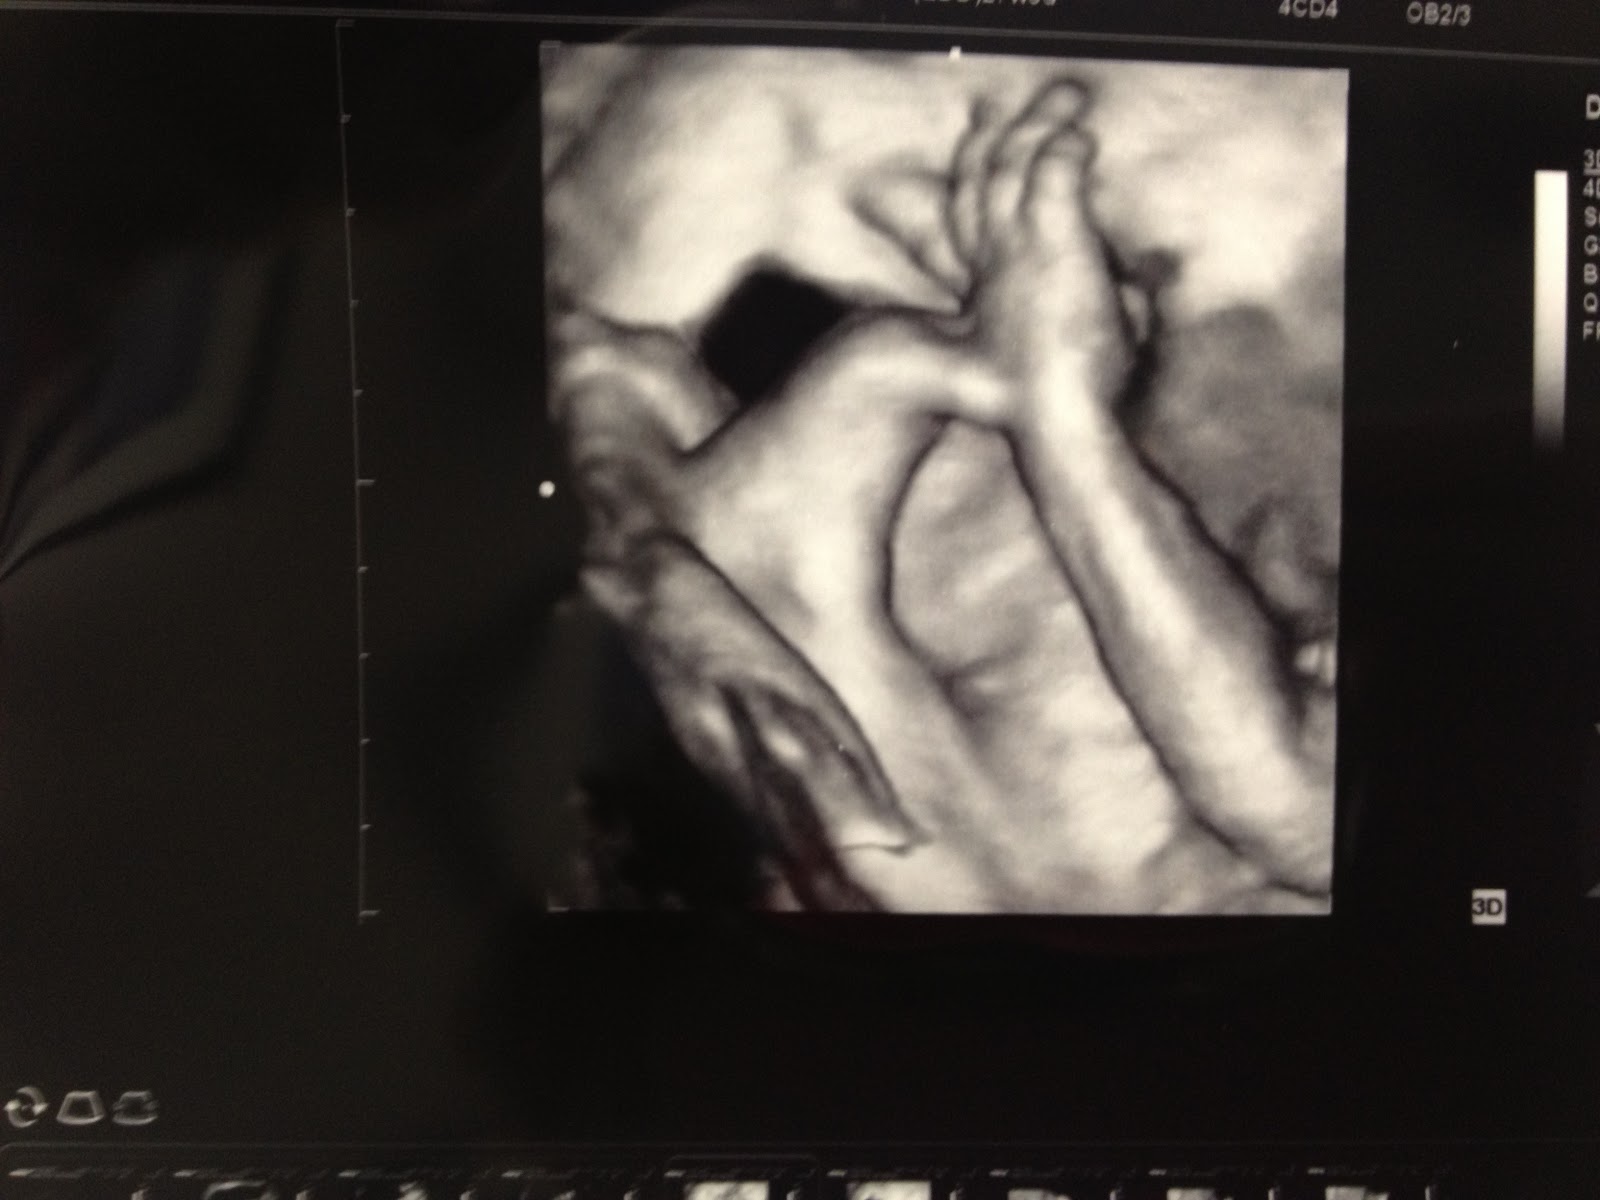

The ultrasound tech did some 3D images too, which was neat because we were able to see some of his features. We weren't expecting that at all, so that was such a nice treat. It is fun seeing/envisioning what he will look like when he is born. We are thinking it looks like he got my nose and Lee's lips. That's all we can tell/predict at this point. Either way- he is amazing!

(playing with his toes)